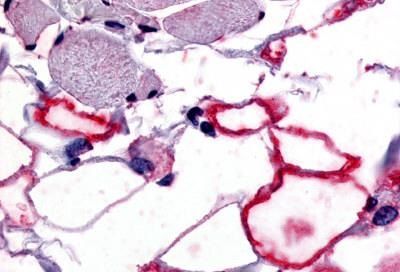

IHC-P analysis of human adipocytes tissue using GTX71161 VIP receptor 1 antibody.

Antigen retrieval : Heat-induced antigen retrieval